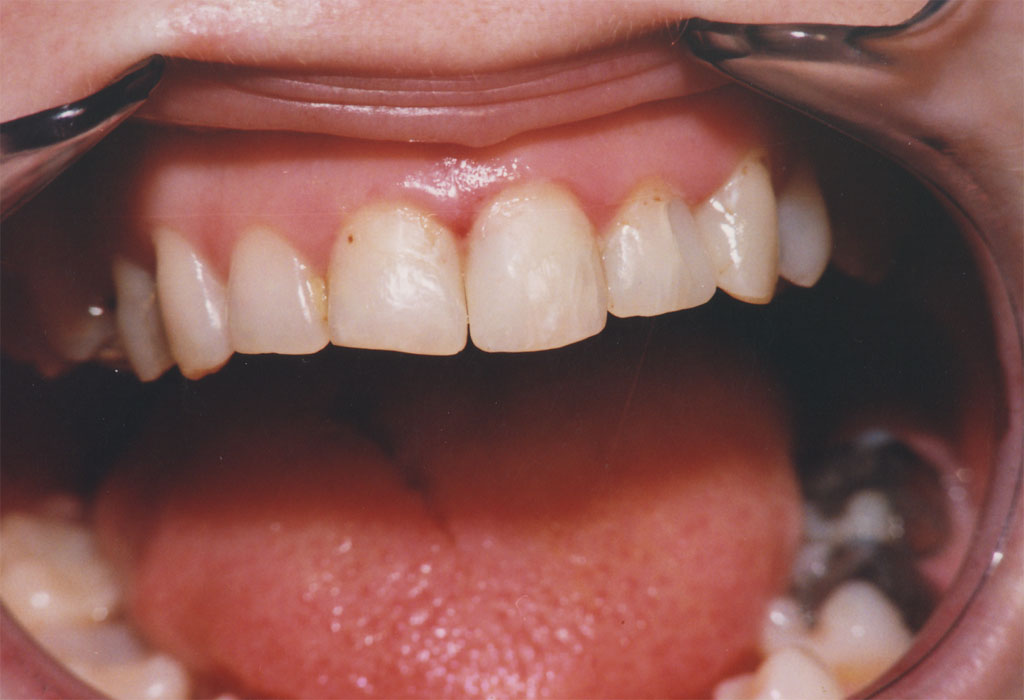

Upotreba savremenih nanohibridnih kompozita renomiranih svetskih proizvođača omugućuje izradu plombi vrhuskog kvaltiteta i estetike.

Rekonstrukcijom zuba po boji, obliku i veličini plombe izgledaju potpuno prirodno i traju dugi niz godina.